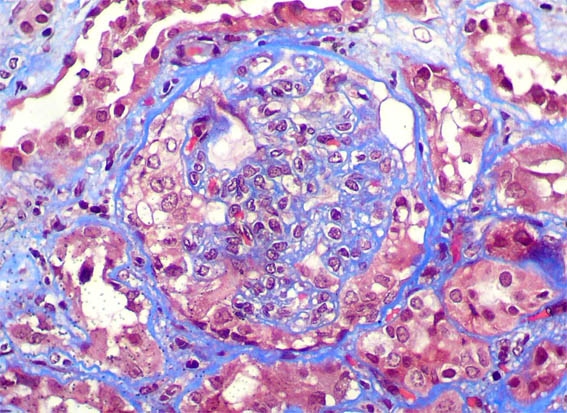

Figure 3.

Masson's

trichrome stain,

X400.